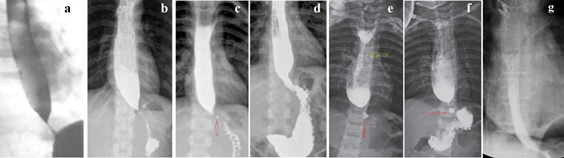

Figure 1 shows EGJ radiographs of patients with mild GERD. As a result of increased pressure in the stomach, the LES has contracted and can be measured as the distance between the esophagus and the stomach that does not contain barium.

Figure 1 The X-ray image of the LES can be detected in GERD during the high pressure in the stomach, which leads to a reflex contraction of the LES. (a) The LES is visible as a zone without contrast agent between the esophagus and stomach. Knowing the height of L-1 at the age of 9 years (2.1 cm), we assume that the height of D -10 (red) is approximately 1.9 cm. Therefore, the length of the LES is 2.2 cm, i.e. equal to the age norm. (b). In the presence of inflammation, a contrast agent remains inside the LES. The cone-shaped end of the esophagus above the LES is a typical picture with GERD. (c) In a vertical position, 3 parts of the LES are shown in different colors (above the diaphragm - yellow, inside the diaphragm - blue, abdominal - red). (d) Phrenic ampulla (f) indicates a wide lumen of the esophagus. PS (proximal sphincter) is a functional sphincter that occurs with GERD. It contracts with ampullar contraction and closes the ampulla so that when it contracts, it can create high pressure between PS and LES. The LES opens at a threshold pressure and the ampulla injects a bolus